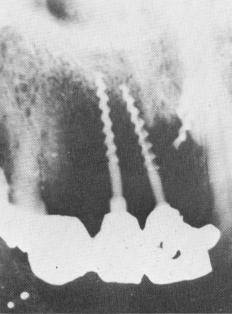

Fig. 14-10. A broken narrow ridge implant is seen leaning toward the neighboring tooth. Broken pieces of implants, although not usually the cause of any problems, should be removed at the same time breakage happens.

1 Broken narrow ridge implant seen leaning towards neighboring tooth